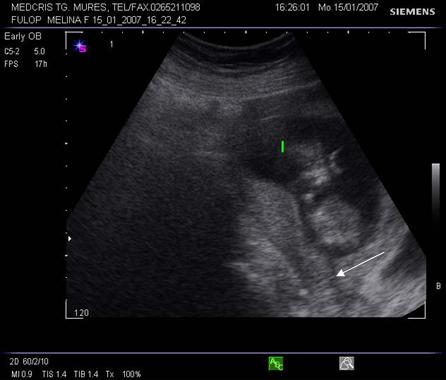

Fig nr 68 Decolare de pol inferior la ecografia abdominala ( sageata )